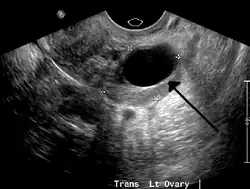

Transvaginal ultrasonography of a hemorrhagic ovarian cyst, probably originating from a corpus luteum cyst. The coagulating blood gives the content a cobweb-like appearance. -